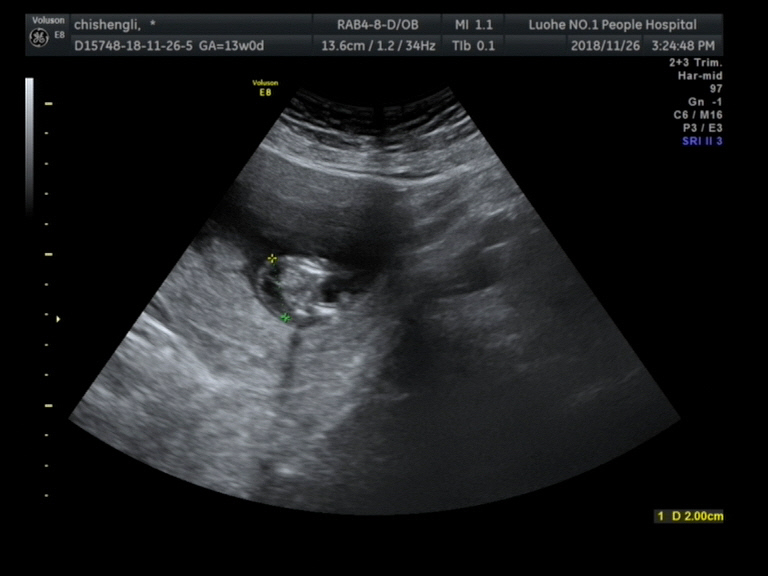

宫腔内可见一胎儿回声,颅骨光环可显示。

双顶径:17mm,头臀长:50mm, 胎动胎心好,胎心率:158次/分,

羊水最深值:33mm,胎盘附着于子宫前壁,厚:12mm, NT:5.4mm.

胎儿颈背部可见一20mmx6.7mm的囊性回声,内可见多条线样高回声分隔,呈多房状改变,CDFI:其内未见明显血流信号。

四腔心切面隐约可见,室间隔上部回声缺失约1mm,静脉导管频谱未见明显异常。